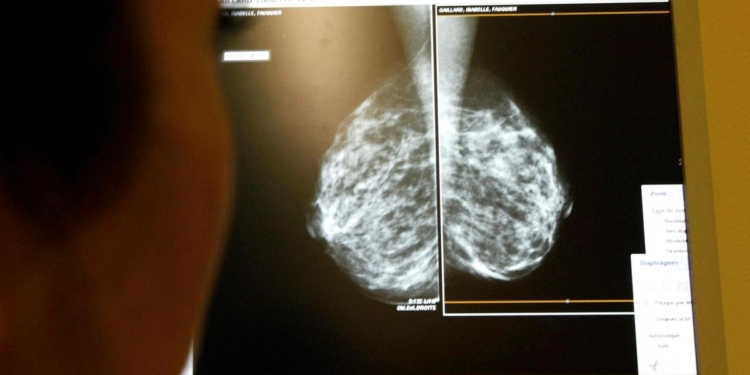

Study demonstrates that metastatic presentation in India is strongly influenced by tumour size, grade, nodal involvement, and lympho-vascular invasion, with health system context modulating the risk